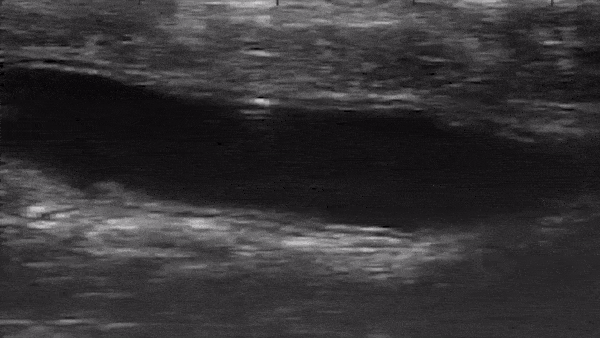

У микробота нет батарейки, он работает от того же магнитного поля, которое контролирует его движение. Команда исследователей смогла продемонстрировать, как разработанный ими механизм передвигается в различных направлениях, при этом за его перемещениями можно следить с помощью аппарата УЗИ.

Испытания проводились на мышах, которых подвергали анестезии: микробота внедряли в толстую кишку, поскольку это наиболее легкая точка доступа внутрь организма, а также потому, что внутренность этого органа, как правило, «завалена» перевариваемой пищей и напитками.